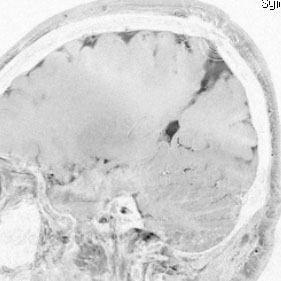

20代の男性の神経細胞腫です。側脳室の中のとても大きな腫瘍です。上段はガドリニウムという造影剤を入れた時のMRIです。下段の中央はCTですが,石灰化が見られます。脳外科の先生には,この脳室内腫瘍は一見transcallosal approach(経脳梁到達法)という手術で取れるように見えるかもしれませんが,そうではなくて,脳室の壁とくに上壁と側壁にくっついているのでなかなか取れません。この患者さんの場合は右の頭頂葉というところからtranscortical approach(経皮質到達法)で全摘出しました。後遺症もなく再発もなく術後10年が過ぎています。全部とれれば治ってしまう腫瘍です。